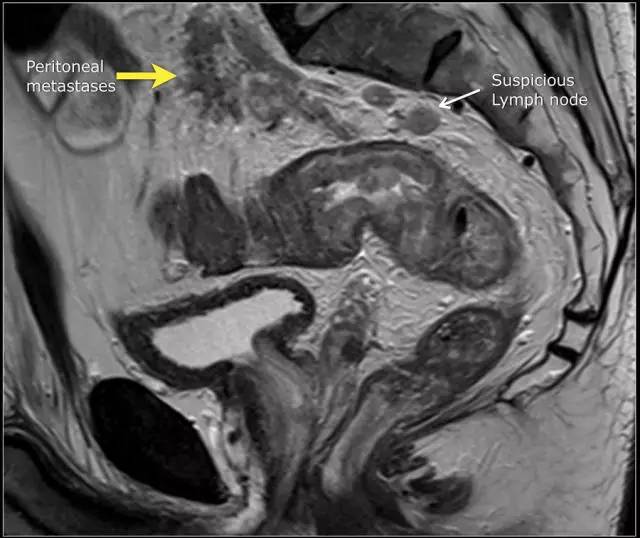

图 14 轴向 T2 加权图像上,沿着内脏腹膜有肿瘤向内生长(箭头)

图 15 同一患者腹膜转移的矢状图(箭头),在直肠内还有可疑的淋巴结